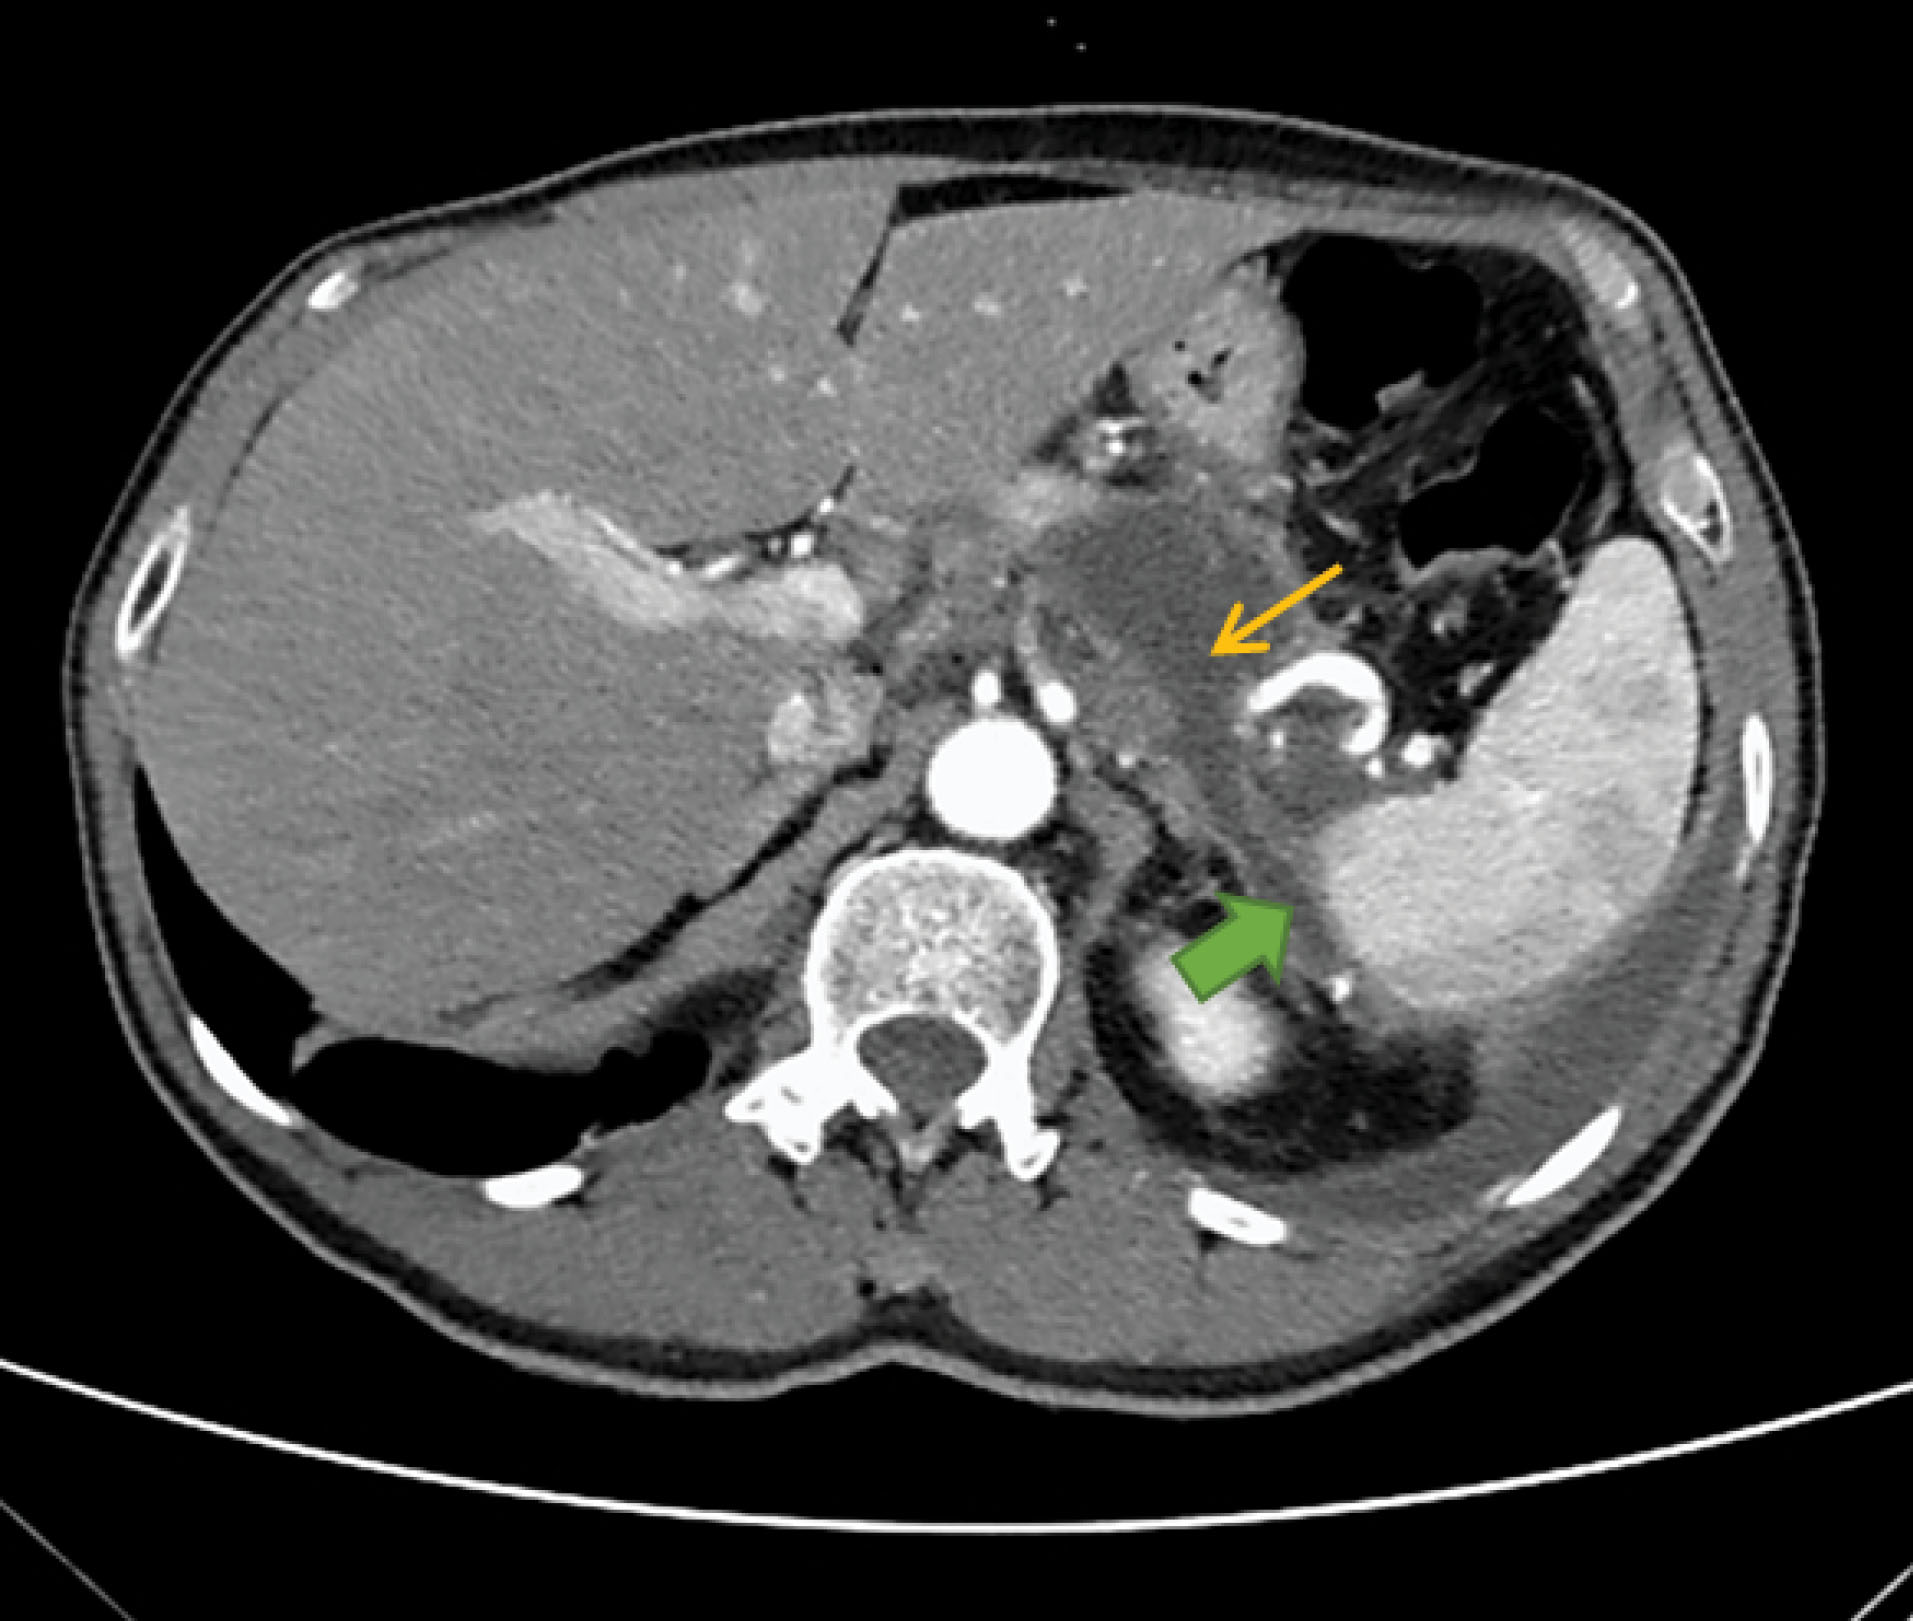

We decided to perform an Abdominal Computed Tomography (CT): at the pancreatic body / tail transition, a collection with 48 x 36 x 46 mm and two drainage paths were observed (). Thus, this findings was suggestive of an acute post-pancreatitis pseudocyst with fistulization to the left pleural cavity and peri-splenic region. He was discharged to General Surgery consultation; however, prior to that MRCP was done, that confirmed the PPF (no suspicium of malignancy).

jcvtr-14-67-g002

Figure 2. Abdominal Computed Tomography (CT) at the time of diagnosis, with evidence of pancreatic pseudocyst (thin yellow arrow) and one of the fistulous paths (full green arrow)